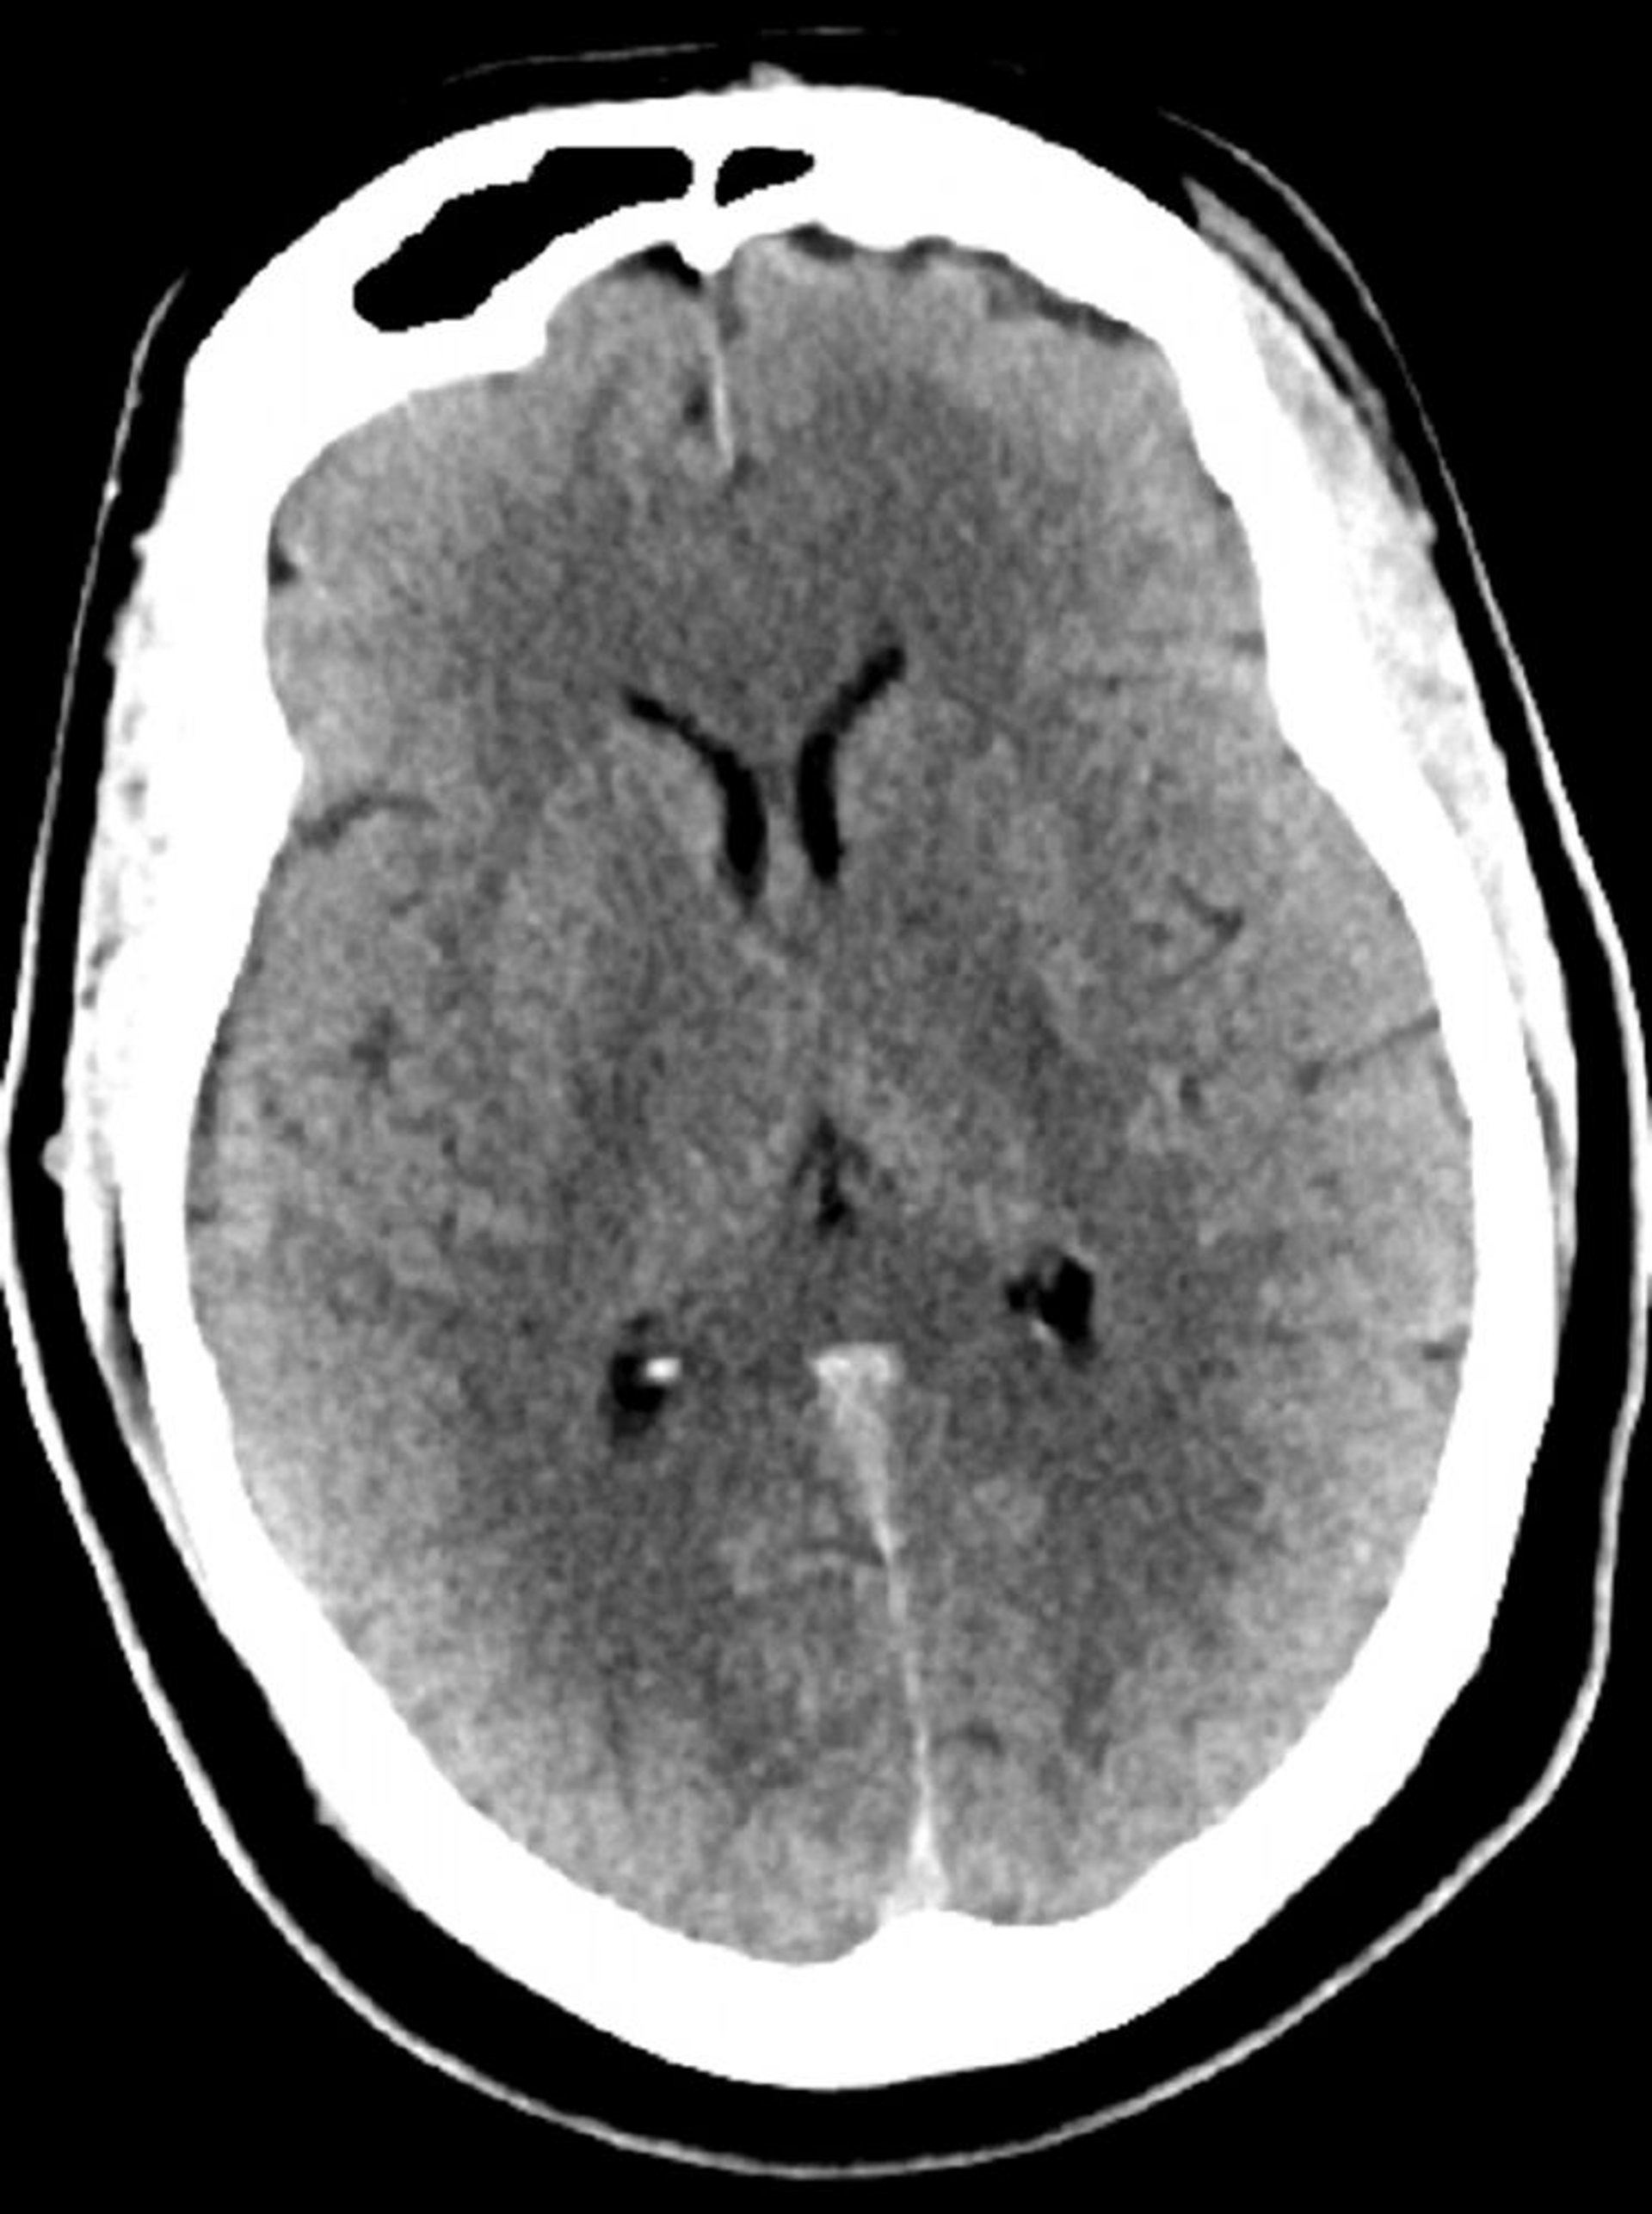

TC cerebrale normale (adulto di 30 anni), slide 5

Questa immagine è una normale TC della testa di un adulto di 30 anni. Non vi è alcun liquido o emorragia intra o extra assiale. La differenziazione grigio-bianca è preservata. Le dimensioni ventricolari e il disegno dei solchi sono normali.